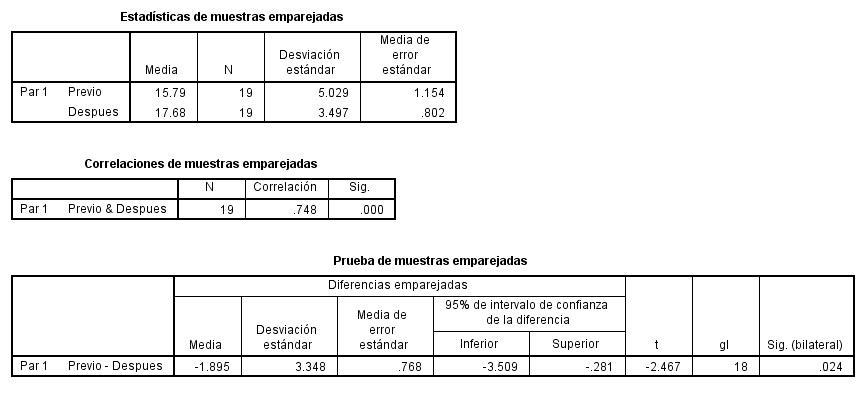

RESULTADOS

RESUMEN

Una de las principales precauciones en la adaptación de lentes de contacto miniesclerales es la zona de aterrizaje, ya que puede llegar a condicionar un bloqueo en la salida del humor acuoso y causar un aumento de la presión intraocular (PIO), que es uno de los principales factores para desarrollar glaucoma. El objetivo del estudio fue identificar el aumento de la PIO en 19 pacientes adaptados con lentes msd®, a los cuales se les realizó una evaluación previa para determinar la variación en el valor de la PIO posterior a una hora de uso del lente diagnóstico. La media de PIO en OD fue 15.63 +4 mmHg y OI 15.79 +5 mmHg; posterior a una hora de uso fue de 17.68 +3.4 mmHg, con significancia P=0.024. Los resultados indican que la PIO posterior al uso durante una hora de lentes miniesclerales aumenta la PIO en promedio 2 mmHg, lo que sugiere que existe una modificación en la dinámica del drenaje del humor acuoso como consecuencia de una posible compresión en la zona de aterrizaje, que hace necesario contar con más estudios para determinar si el aumento de la PIO se mantiene durante el uso prolongado de este tipo de lentes Palabras clave: Presión Intraocular, Lentes de Contacto Esclerales, Miniesclerales, RGP, Agudeza Visual, Humor Acuoso, OCT, Optometría, Oftalmología.

Para el análisis estadístico einterpretación de la información, se realizó una estadística paramétrica utilizando una t-student para muestrasrelacionadas conunvalordesignificancia de p <0.05

RESULTADOS

Se cuenta con una muestra de 19 pacientes, de los cuales 11 son mujeres y 8 son hombres, con un rango de edad de 18-45 años de edad, conunamediana de20añosyunamediade 24.42 años y una desviación estándar SD de 8.262

Previa inserción de la LC escleral, se registró individualmente la PIO del ojo derecho ojo control de cada paciente, obteniendo una media de 15,63 mmHg con una desviación SD 4,0099 asociada a un rango de 10 a 23 mmHg (Figura 1).

En ojo izquierdo se obtuvo una PIO media pre inserción de la LC escleral correspondiente a 15,79 mmHg, con un rango de 10 a 24 mmHg (Tabla 1 y Figura 2).

Figura2.PIOdeojoizquierdoantesdeusodelaLCminiescleralMSD® Después del uso de 60 minutos de la LC escleral en ojo izquierdo, se registró una PIO media de 17,68 mmHg con un rango de distribución de frecuencias de 12 a 24 mmHg (Tabla 2 y Figura 3).

Los resultados revelan modificaciones de la PIO después de una hora de uso de la LC escleral msd® , considerando la PIO media en ojo izquierdo previa a la inserción (15.79 mmHg), y la alcanzada después de una hora de uso (17.68 mmHg), lo que representó un incremento de 1,89 mmHg.

En tal sentido, el nivel de significancia establecido mediante la prueba de t-student,

reveló que el aumento de la PIO después de una hora de uso de la LC escleral constituye una diferenciasignificativa(p=0.024), sugestivadeque el uso de las LC esclerales genera efectos directos en el valor de la PIO en este caso, incremento después de una hora de uso (Tabla 3).